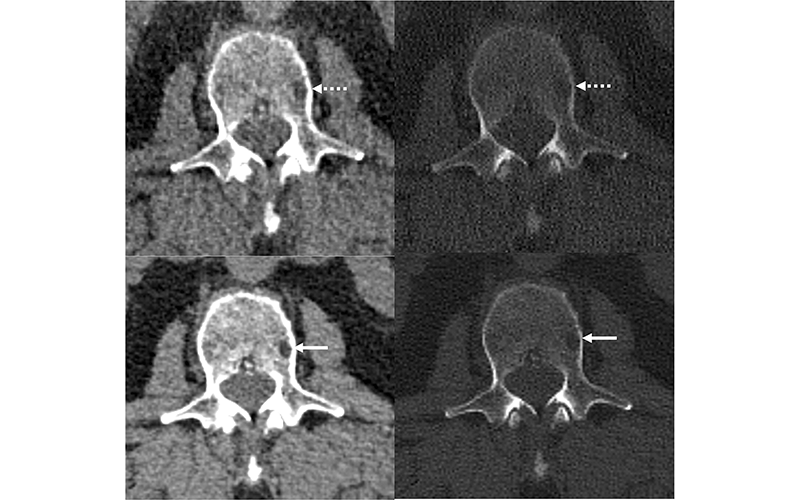

In the Radiology study, he and his fellow researchers found that imaging features of myeloma were depicted more clearly on photon-counting detector images compared with energy-integrating detector images.

“We believe that the lower image noise and higher intrinsic spatial resolution of the photon-counting detector images led to sharper lesion margins and better image contrast,” he said. “In phase two of the study (with photon- counting detector images at thinner image sections of 0.6 mm and deep learning denoising), the radiologists detected more lytic lesions compared to energy-integrating scans.”